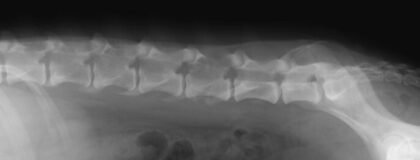

In diesem vetinar werden gemeinsam unterschiedliche orthopädische und neurologische Fälle mit Fokus auf den Aspekt der Bildgebenden Diagnostik bearbeitet. Spezielle Erkrankungen und deren Röntgencharakteristika und Ultraschallbefunde werden unterstützt durch Informationen aus den Schnittbildverfahren anhand von Fallbeispielen demonstriert. Anhand der Befunde werden „Entscheidungs Algorithmen“ und der Aufbau der Differentialdiagnosenliste diskutiert. Der Abschluss wird durch Tipps zum Transfer in den Alltag gebildet.